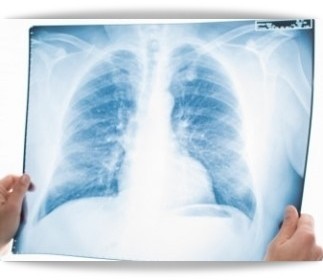

폐렴 초기증상

폐렴 초기증상의 대표적인 문제는 역시 기침과 가래입니다. 일상 속에서 꾸준한 기침과 가래를 유발할 수 있고 가래는 더욱 끈적하고 고름처럼 나오기도 합니다.

6) 호흡곤란

폐에 발생하는 성인 폐렴 증상인 만큼 해당 문제로 인해 호흡곤란을 느낄 수 있습니다. 예전에 비해서 호흡 자체에 불편함을 느끼고 통증이 느껴지는 경우도 있습니다.